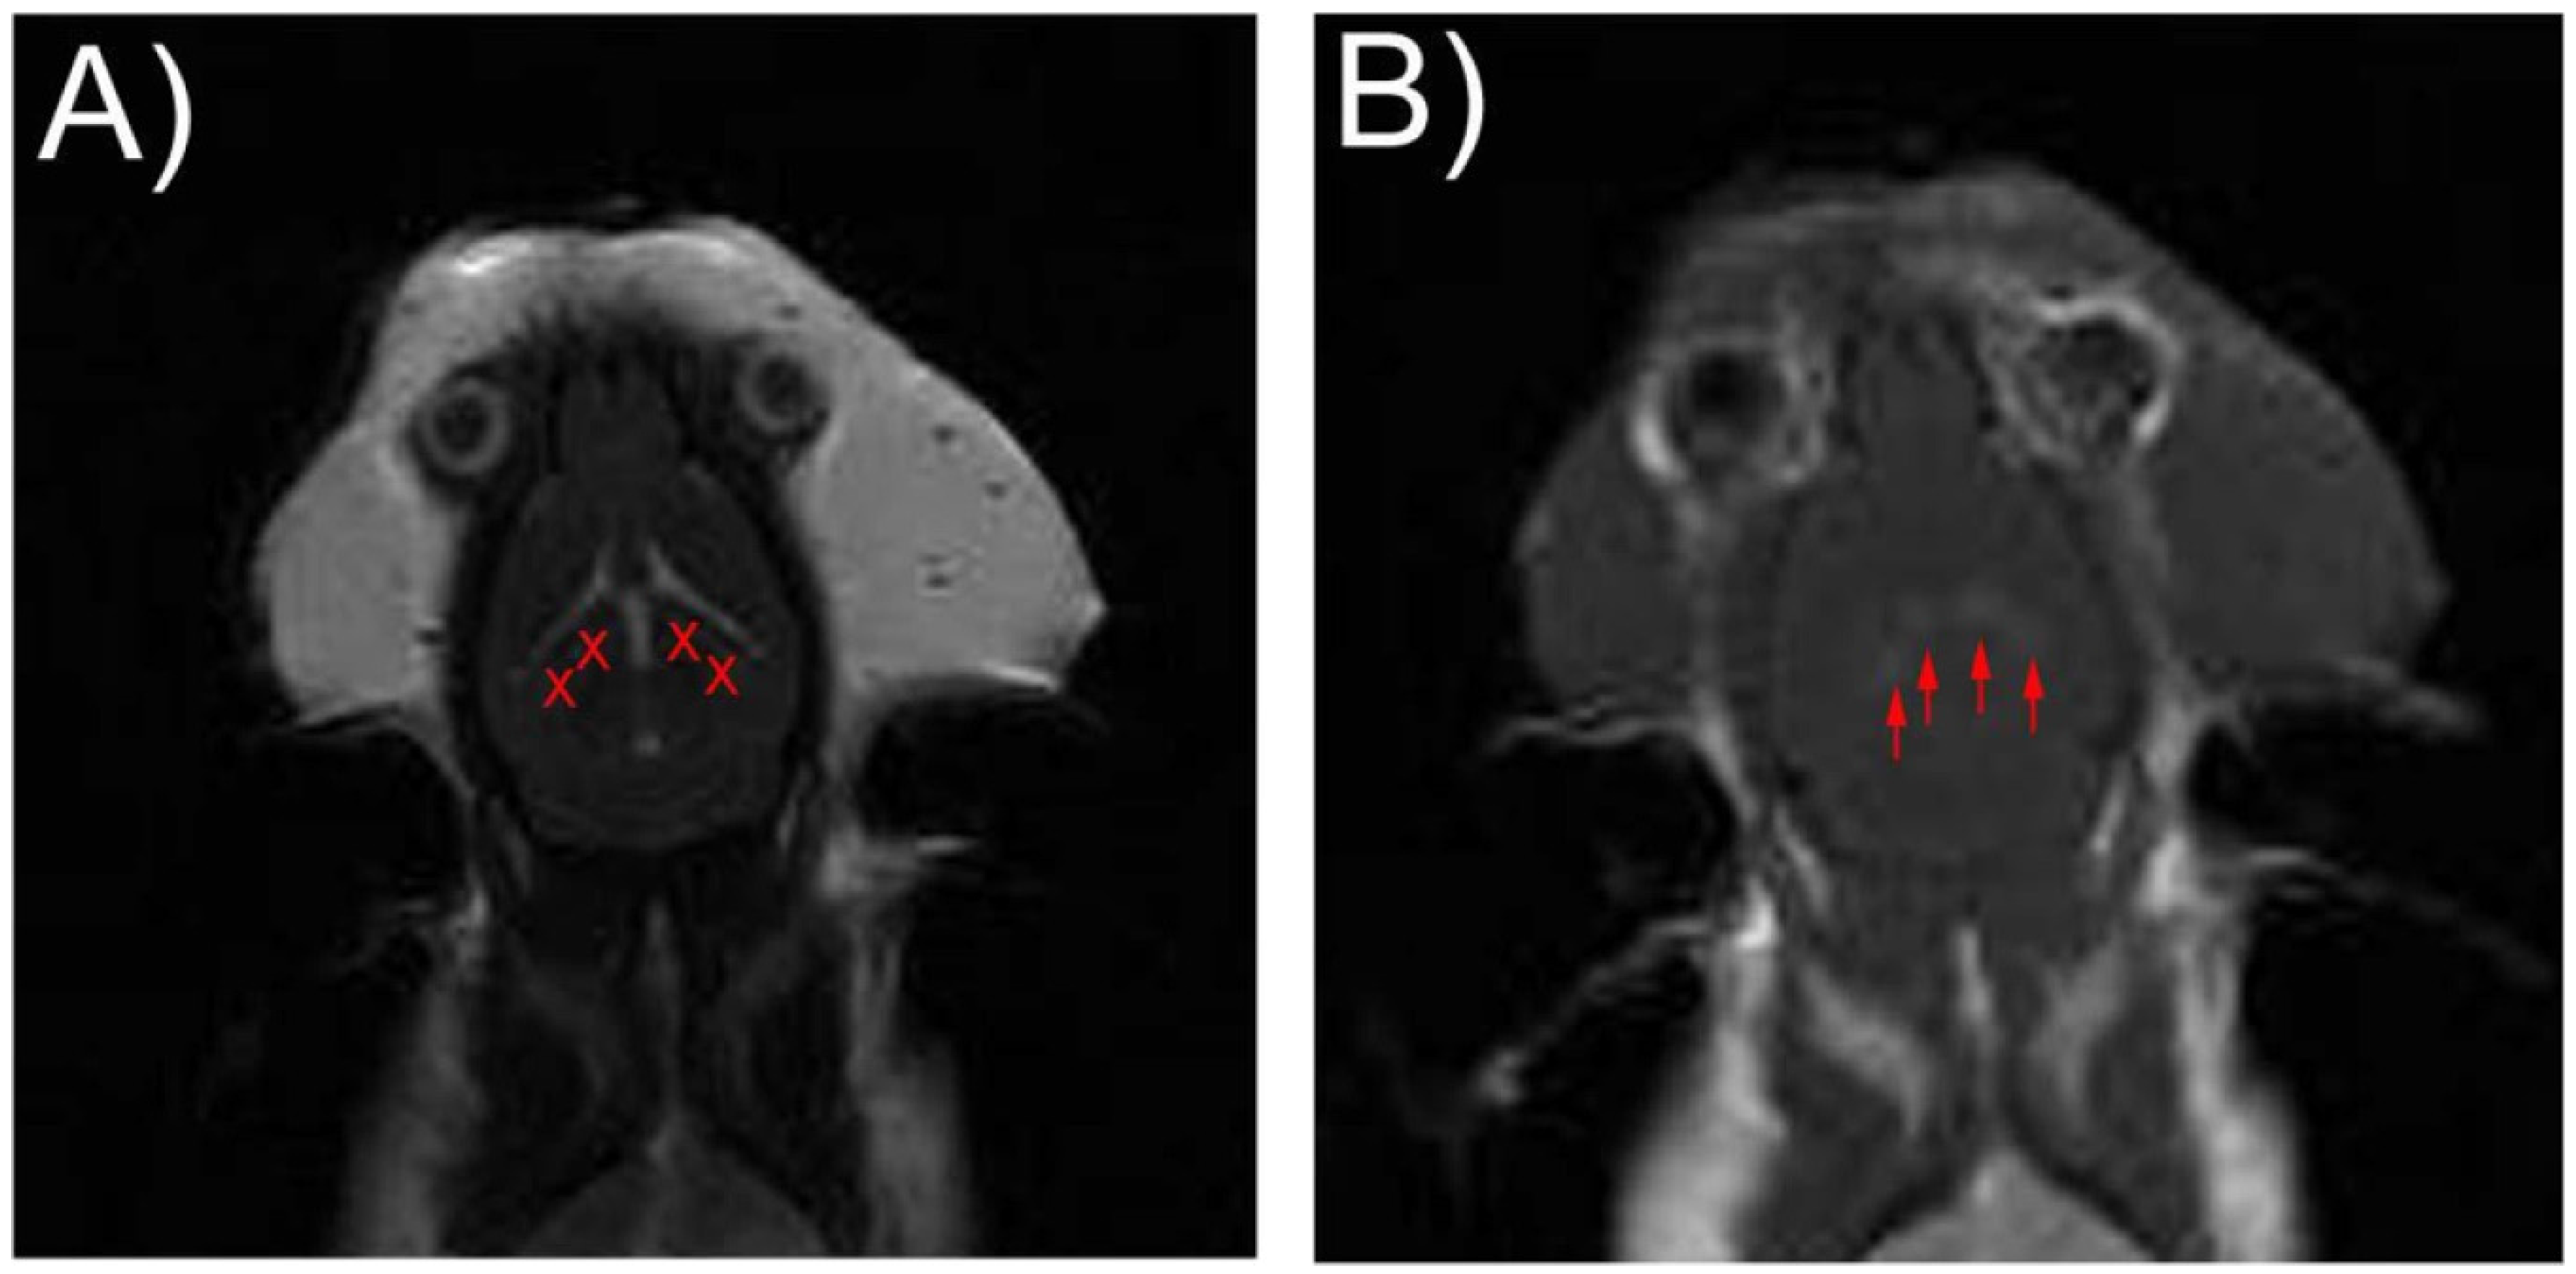

2.4. Blood-Brain Barrier Disruption